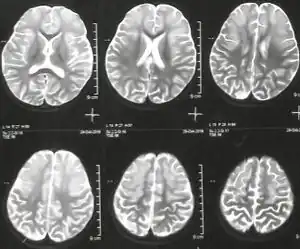

Argininemia is an autosomal recessive urea cycle disorder where a deficiency of the enzyme arginase causes a buildup of arginine and ammonia in the blood. Ammonia, which is formed when proteins are broken down in the body, is toxic if levels become too high; the nervous system is especially sensitive to the effects of excess ammonia.[2][6]

- Microcephaly

The ARG1 gene provides instructions for making an enzyme called arginase, this enzyme controls the last steps of the urea cycle, which produces urea by extracting nitrogen from arginine.[4] In people with arginase deficiency, arginase is missing, and arginine is not broken down properly. consequently, urea cannot be produced and excess nitrogen accumulates in the blood in the form of ammonia. Ammonia and arginine are thought to cause neurological problems and other symptoms of arginase deficiency.[2]